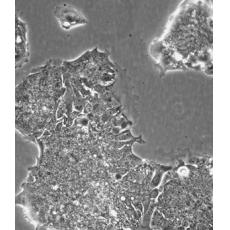

中文名稱 人結(jié)腸腺癌肺轉(zhuǎn)移細胞

組織來源 結(jié)腸腺癌;肺轉(zhuǎn)移;男性

生長特性 adherent

形態(tài)特征 epithelial

細胞描述 T84細胞株是從一位72歲男性結(jié)腸癌患者的肺轉(zhuǎn)移灶建立的可移植人類癌細胞株。 腫瘤組織皮下接種于BALB/c裸鼠,并連續(xù)進行移植。 [26072] 在裸鼠身上的移植過程中,細胞株始終保持結(jié)腸癌的原始組織性狀。 [26072] 在無胸腺小鼠中傳代23代后建立了T84細胞株。 這些細胞單層生長到飽和并在接觸細胞間展現(xiàn)出緊密連接和橋粒。 [1155] 有很多關(guān)于多肽類激素和神經(jīng)遞質(zhì)并維持定向電解質(zhì)傳輸?shù)氖荏w。 [1155] 這株細胞展現(xiàn)了接觸細胞中的緊密連接和橋粒。 [1155] 角蛋白免疫過氧化物酶染色陽性。